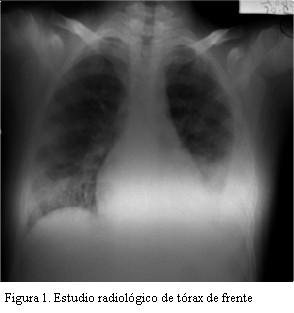

Escolar de 11 años. Buen crecimiento y desarrollo. Bien inmunizado. Sin antecedentes patológicos personales a destacar, niega uso de drogas intravenosas, nunca internaciones. Ingresa a sala de pediatría por síndrome toxoinfeccioso de 5 días de evolución, dado por fiebre de hasta 40ºC axilar y marcada adinamia, con mialgias intensas en reposo y a la movilización. En sala persiste febril (hasta 40ºC axilar), artromialgias y postración, agregando tos seca y dolor tipo puntada de lado en hemitórax izquierdo, el estudio radiológico (figura 1) muestra imagen compatible con derrame pleural. Se inicia penicilina G cristalina IV a 400.000 UI/kg/día. En los días siguientes mantiene fiebre alta en picos, estado de postración con gran repercusión general, agrega ictericia de tipo colestásico y mayor compromiso respiratorio, por lo que ingresa a la unidad de cuidados intermedios (CI) a los 7 días de internación. Al ingreso a la misma se destaca: febril, ictericia generalizada, recibe oxígeno por catéter nasal, frecuencia respiratoria 36 pm, saturación 98%. Frecuencia cardíaca 115 pm, presión arterial: 91/65/40, pulsos llenos, tiempo de recoloración 1 s. Palidez cutáneo mucosa. Artromialgias intensas con dolor a la movilización, estado de postración. Al examen pleuropulmonar: síndrome en menos en base de hemitórax izquierdo con tubo de drenaje de tórax constatándose gasto de líquido serohemático. Cardiovascular: no frémitos, ritmo regular de 115 pm, tonos bien golpeados, no soplos. No edemas de miembros inferiores. No ingurgitación yugular, ni reflujo hepatoyugular. Hepatomegalia regular con franco aumento de la consistencia. A nivel de miembros inferiores: lesiones de impétigo evolucionadas en etapa de cicatrización. Resto del examen normal. Paraclínica al ingreso: pH 7,45, pCO2 37,8, pO2 71 venosa, HCO3 25, BE 1,8, saturación 95%. Hematocrito: 25%, hemoglobina: 8,9 g/dl, glóbulos blancos: 19.400 elementos/mm3, 92% de granulocitos, plaquetas: 163.000 elementos/mm3. VES: 145 mm 1a. hora. Urea: 57 mg/dl, creatinina: 0,68 mg/dl. Bilirrubina total: 7,2 mg/dl, directa: 6,5 mg/dl, TGO: 28 UI/l, TGP: 27 UI/l.